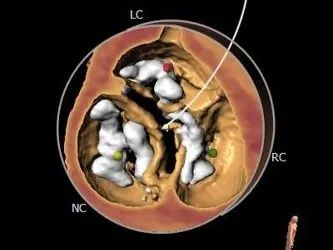

术前CT评估:

主动脉根部评估:

冠脉评估:

钙化评估:

重度钙化,左冠窦钙化延伸至LVOT水平

血管入路评估: